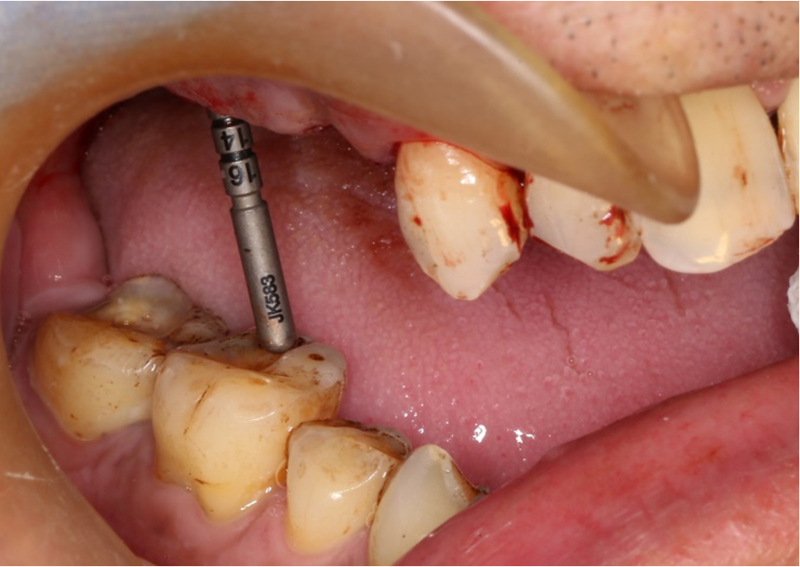

檢查:患者14、15、16、17缺失,無紅腫潰瘍,牙齦情況良好,口腔衛(wèi)生狀況良好。

診斷:14、15、16、17缺失

處理:通過數(shù)字化種植導航進行15、16、17種植修復

®按照術前方案進行備洞及植體植入

®按照術前方案進行備洞及植體植入,醫(yī)生可以通過屏幕軟件引導對手術中植入點、角度、深度實時追蹤

®對植體深度及方向進行確認